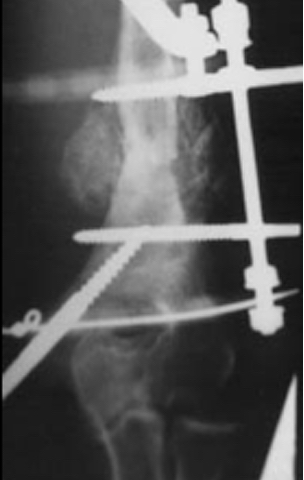

1. Deformite ile birlikte Sert Psödoartroz

Bu tip psödoartrozlar genelikle yetersiz stabilite sonucu oluşmuşlardır. Patolojinin tedavisinde prensip, tedrici olarak deformitenin düzeltilmesi ve bir miktar distraksiyonla (monofokal distraksiyon osteogenezi) kallus oluşumunun stimülasyonudur. Deformite düzeltme prensiplerinden de bilindiği üzere eğer ekstremitede kısalık da mevcut ise menteşeler deformitenin konveks tarafında açı ortay üzerine yerleştirilmelidir. Psödoartroz hattı günde 0.5 mm distraksiyon yapacak şekilde ayarlanmalıdır. Çünkü klinik tecrübemiz sert psödoartrozlarda 1 mm / gün yapılacak bir distraksiyonun ağrıya sebep olacağıdır.